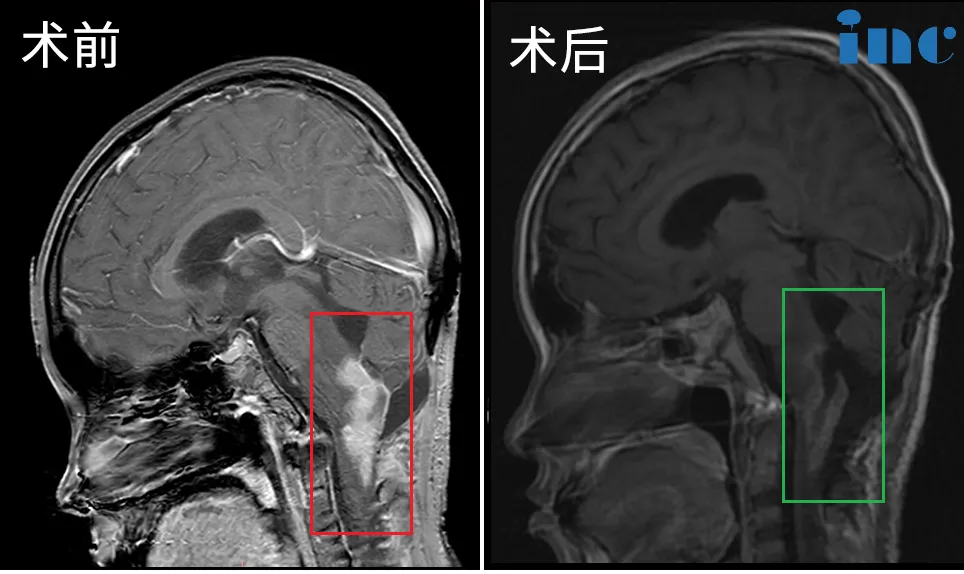

然然术前术后影像对比